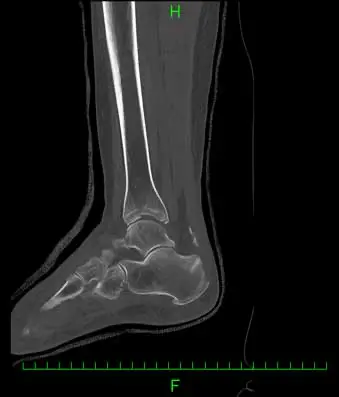

(図2)CT

足関節内外果骨折、脛骨天蓋部に5mmのstep offを伴う陥没骨折と踵骨アキレス腱付着部より1.5cm近位に骨片を認める。